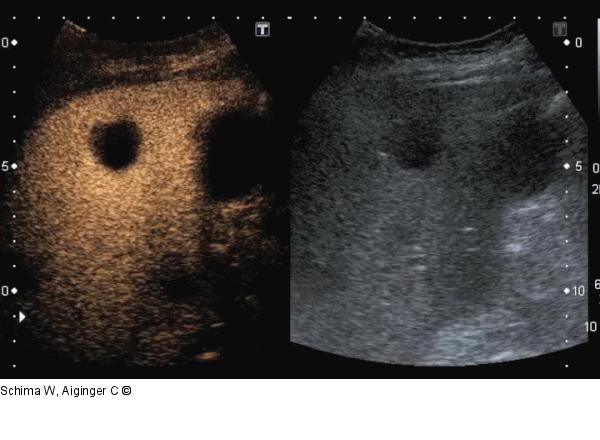

Abbildung 7: Film 3 Kontrastmittelsonographie der Leber im Dualbildmodus (rechts: CEUS; links: normale B-Bild-Sonographie): Die Abszesse zeigen keinen Kontrastmittel- Wash-in oder -Wash-out im Zentrum. |

Kontrastmittelsonographie der Leber im Dualbildmodus (rechts: CEUS; links: normale B-Bild-Sonographie): Die Abszesse zeigen keinen Kontrastmittel- Wash-in oder -Wash-out im Zentrum. |